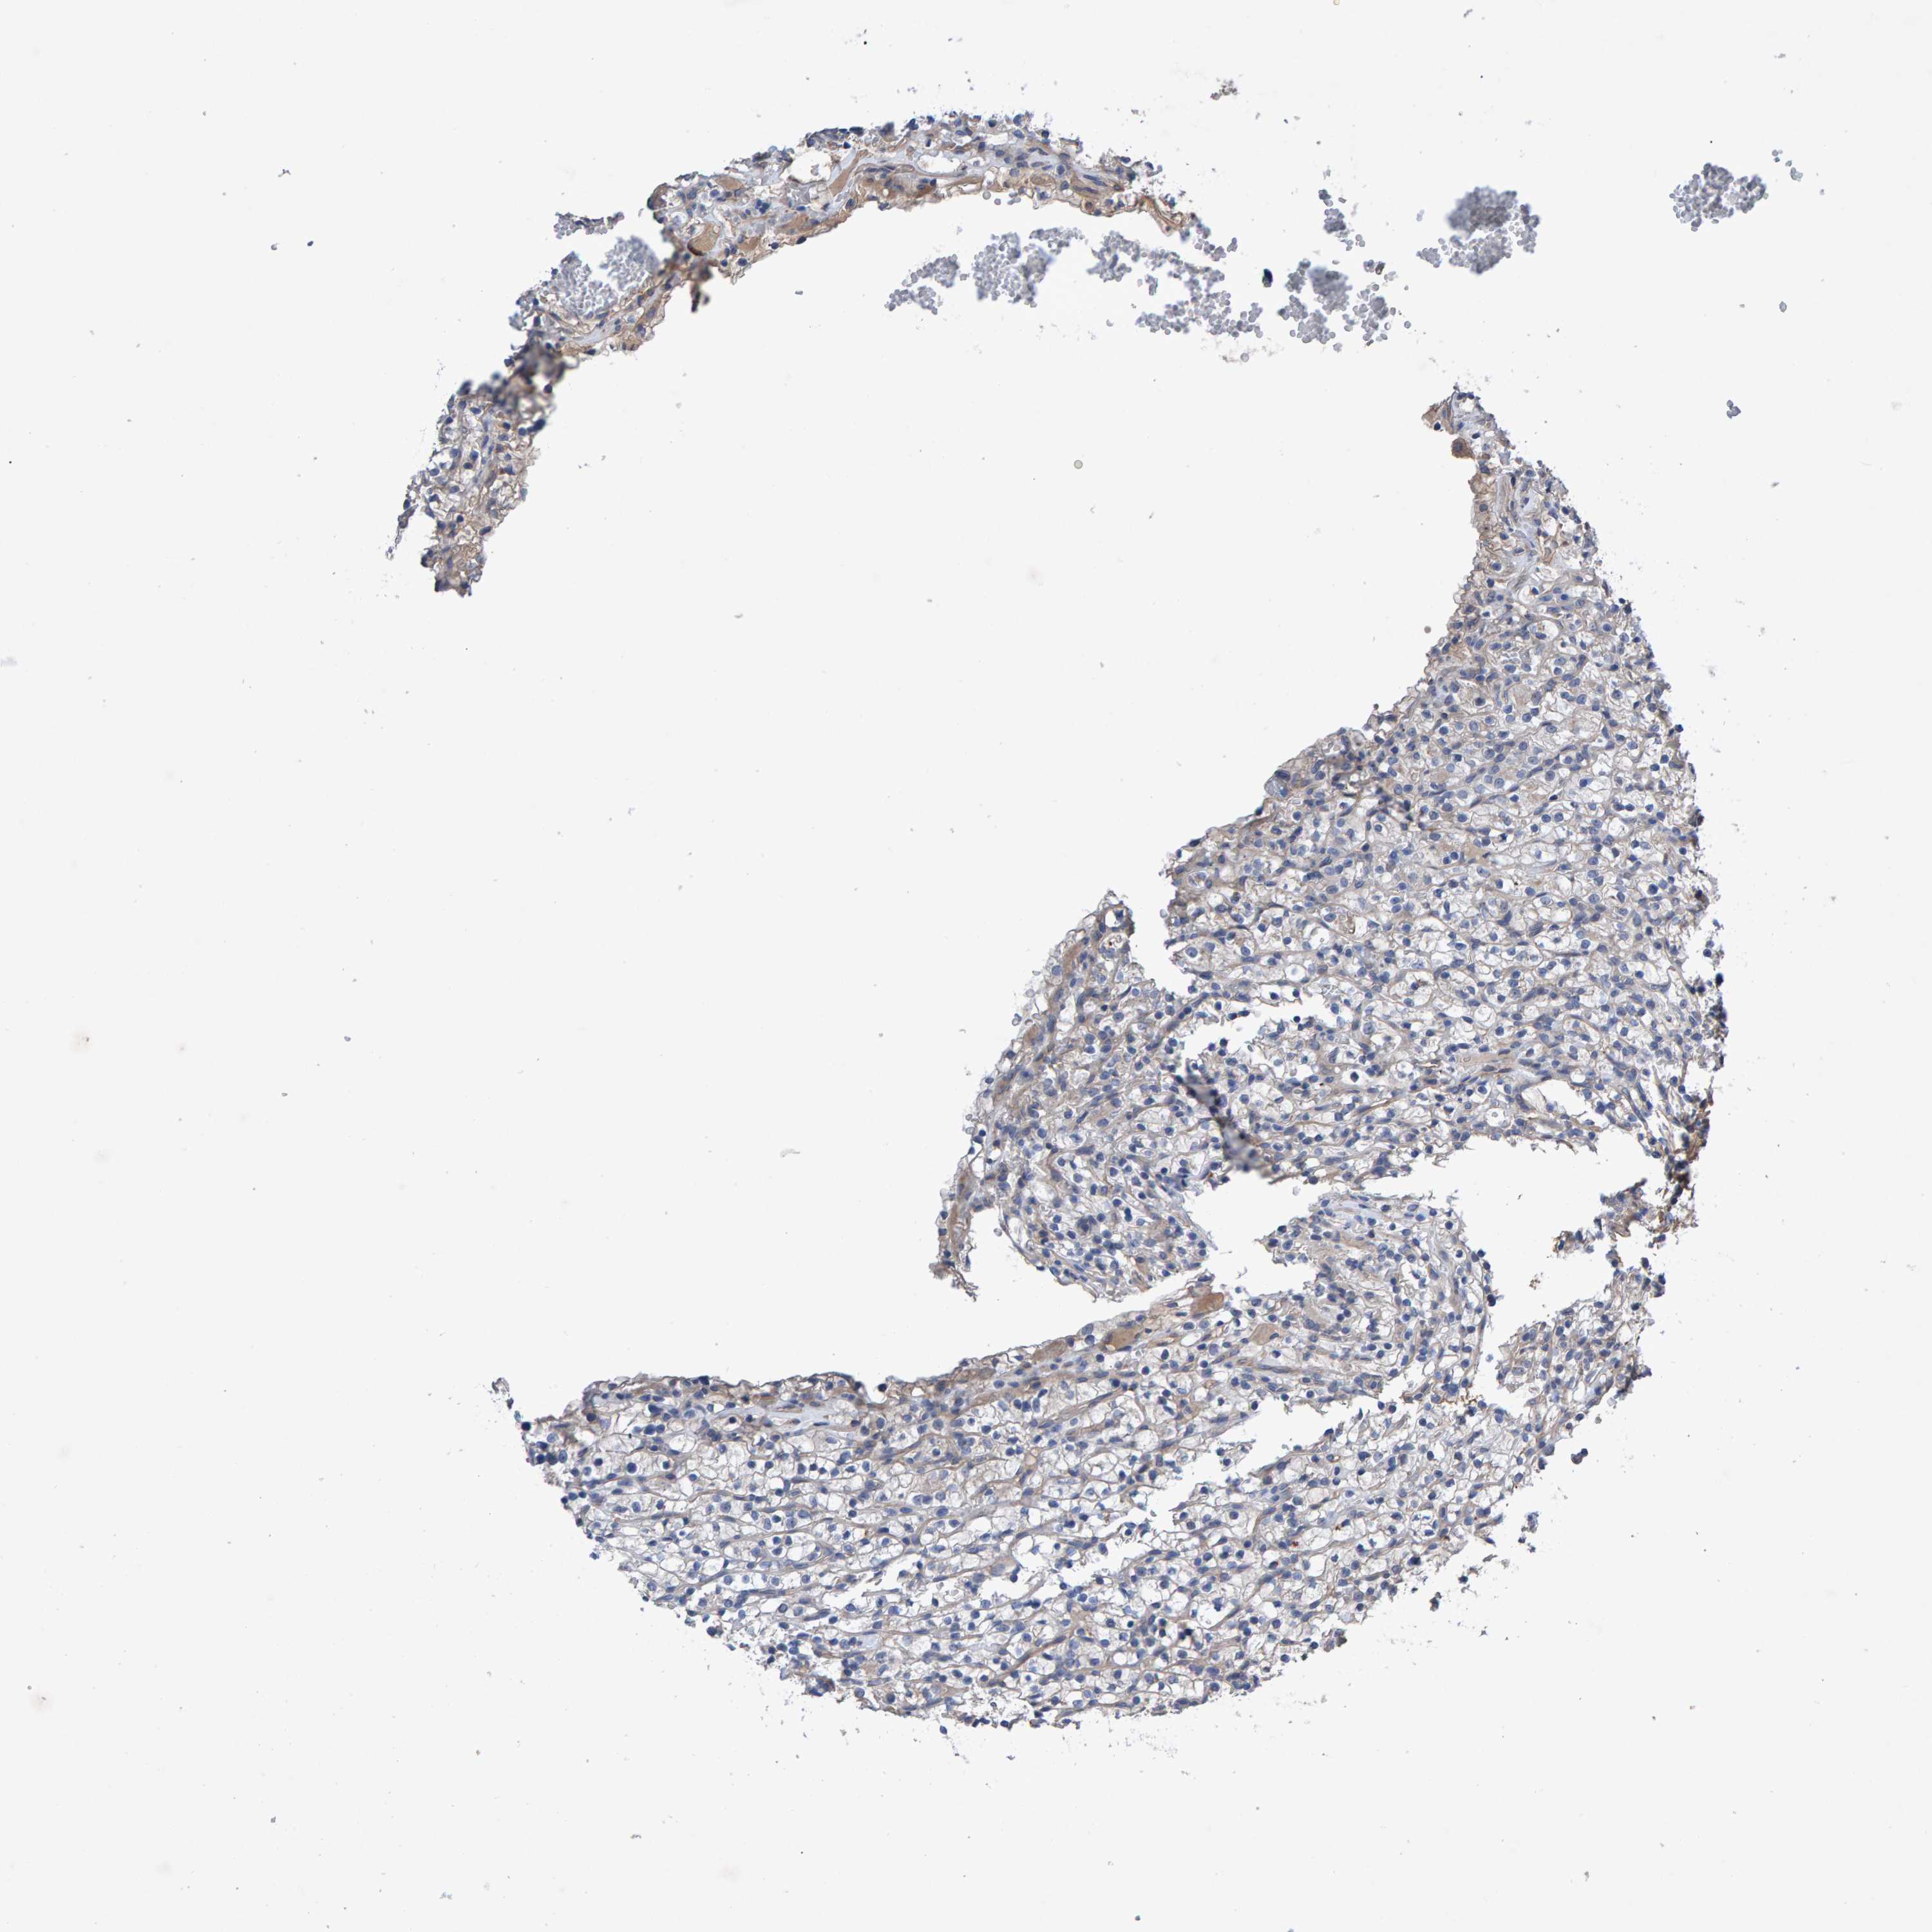

KIDNEY RENAL CLEAR CELL CARCINOMA (TCGA) - Interactive survival scatter ploti

The Survival Scatter plot shows the clinical status (i.e. dead or alive) for all individuals in the patient cohort, based on the same data that underlies the corresponding Kaplan-Meier plots. Patients that are alive at last time for follow-up are shown in blue and patients who have died during the study are shown in red.

The x-axis shows the expression levels (FPKM) of the investigated gene in the tumor tissue at the time of diagnosis. The y-axis shows the follow-up time after diagnosis (years). Both axes are complimented with kernel density curves demonstrating the data density over the axes. The top density plot shows the expression levels (FPKM) distribution among dead (red) and alive patients (blue). The right density plot shows the data density of the survived years of dead patients with high and low expression levels respectively, stratified using the cutoff indicated by the vertical dashed line through the Survival Scatter plot. This cutoff is automatically defined based on the FPKM cutoff that minimizes the p-score. The cutoff can be changed by dragging the vertical line or by entering a cutoff value in the square labeled "Current cut-off".

Under the Survival Scatter plot the p-score landscape (black curve; left axis) is shown together with dead median separation (red curve; right axis). Dead median separation is the difference in median mRNA expression between patients who have died with high and low expression, respectively. It is calculated as follows: median FPKM expression of dead patients with high expression - median FPKM expression of dead patients with low expression. This is intended to aid the user in visually exploring custom cutoffs and the associated p-scores and dead median separation.

Individual patient data is displayed and can be filtered by clicking on one or more of the category buttons on the top of the page. Categories describing expression level and patient information include: high, low, alive, dead, female, male and tumor stages. The scale of the x-axis can be toggled between linear and log-scale by clicking on the "x log" button. Mouse-over function shows TCGA ID, patient information and mRNA expression (FPKM) for each patient.

& Survival analysisi

Kaplan-Meier plots summarize results from analysis of correlation between mRNA expression level and patient survival. Patients were divided based on level of expression into one of the two groups "low" (under cut off) or "high" (over cut off). X-axis shows time for survival (years) and y-axis shows the probability of survival, where 1.0 corresponds to 100 percent.

EFR3A is potential prognostic, high expression is favorable in Kidney Renal Clear Cell Carcinoma (TCGA)

Best expression cut offi

Based on the FPKM value of each gene, patients were classified into two groups and association between prognosis (survival) and gene expression (FPKM) was examined. The best expression cut-off refers the FPKM value that yields maximal difference with regard to survival between the two groups at the lowest log-rank P-value. Best expression cut-off was selected based on survival analysis .

When clicking on this number, the vertical dashed line indicating cut-off, the interactive survival plot, and the Kaplan-Meier curve will be adjusted to show results based on the best expression cut-off.

: 20.32

P scorei

Log-rank P value for Kaplan-Meier plot showing results from analysis of correlation between mRNA expression level and patient survival.

N/A

TCGA RNA samplesi

RNA-seq data is reported as average FPKM (number Fragments Per Kilobase of exon per Million reads), generated by the The Cancer Genome Atlas (TCGA) .

Normal distribution across the dataset is visualized with box plots, shown as median and 25th and 75th percentiles. Points are displayed as outliers if they are above or below 1.5 times the interquartile range. FPKM values of the individual samples are presented next to the box plot.

Average pTPM 26.6

Number of samples 521